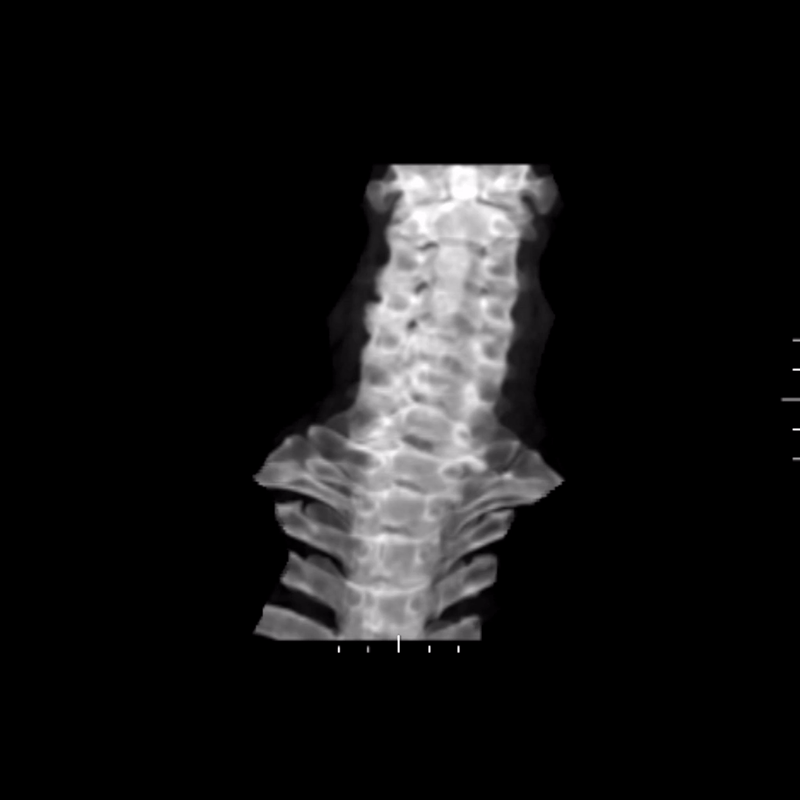

Using the CT dataset, a radiologic technologist processed the images to create a series of advanced visualizations that highlight the distribution of ossification and its relationship to surrounding anatomy. These images provide different perspectives of the cervical spine and help translate cross-sectional findings into more intuitive views.

Figure D: Grayscale rotational volume render of the spine.